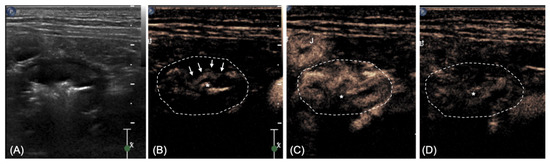

2.2. Imaging Diagnosis